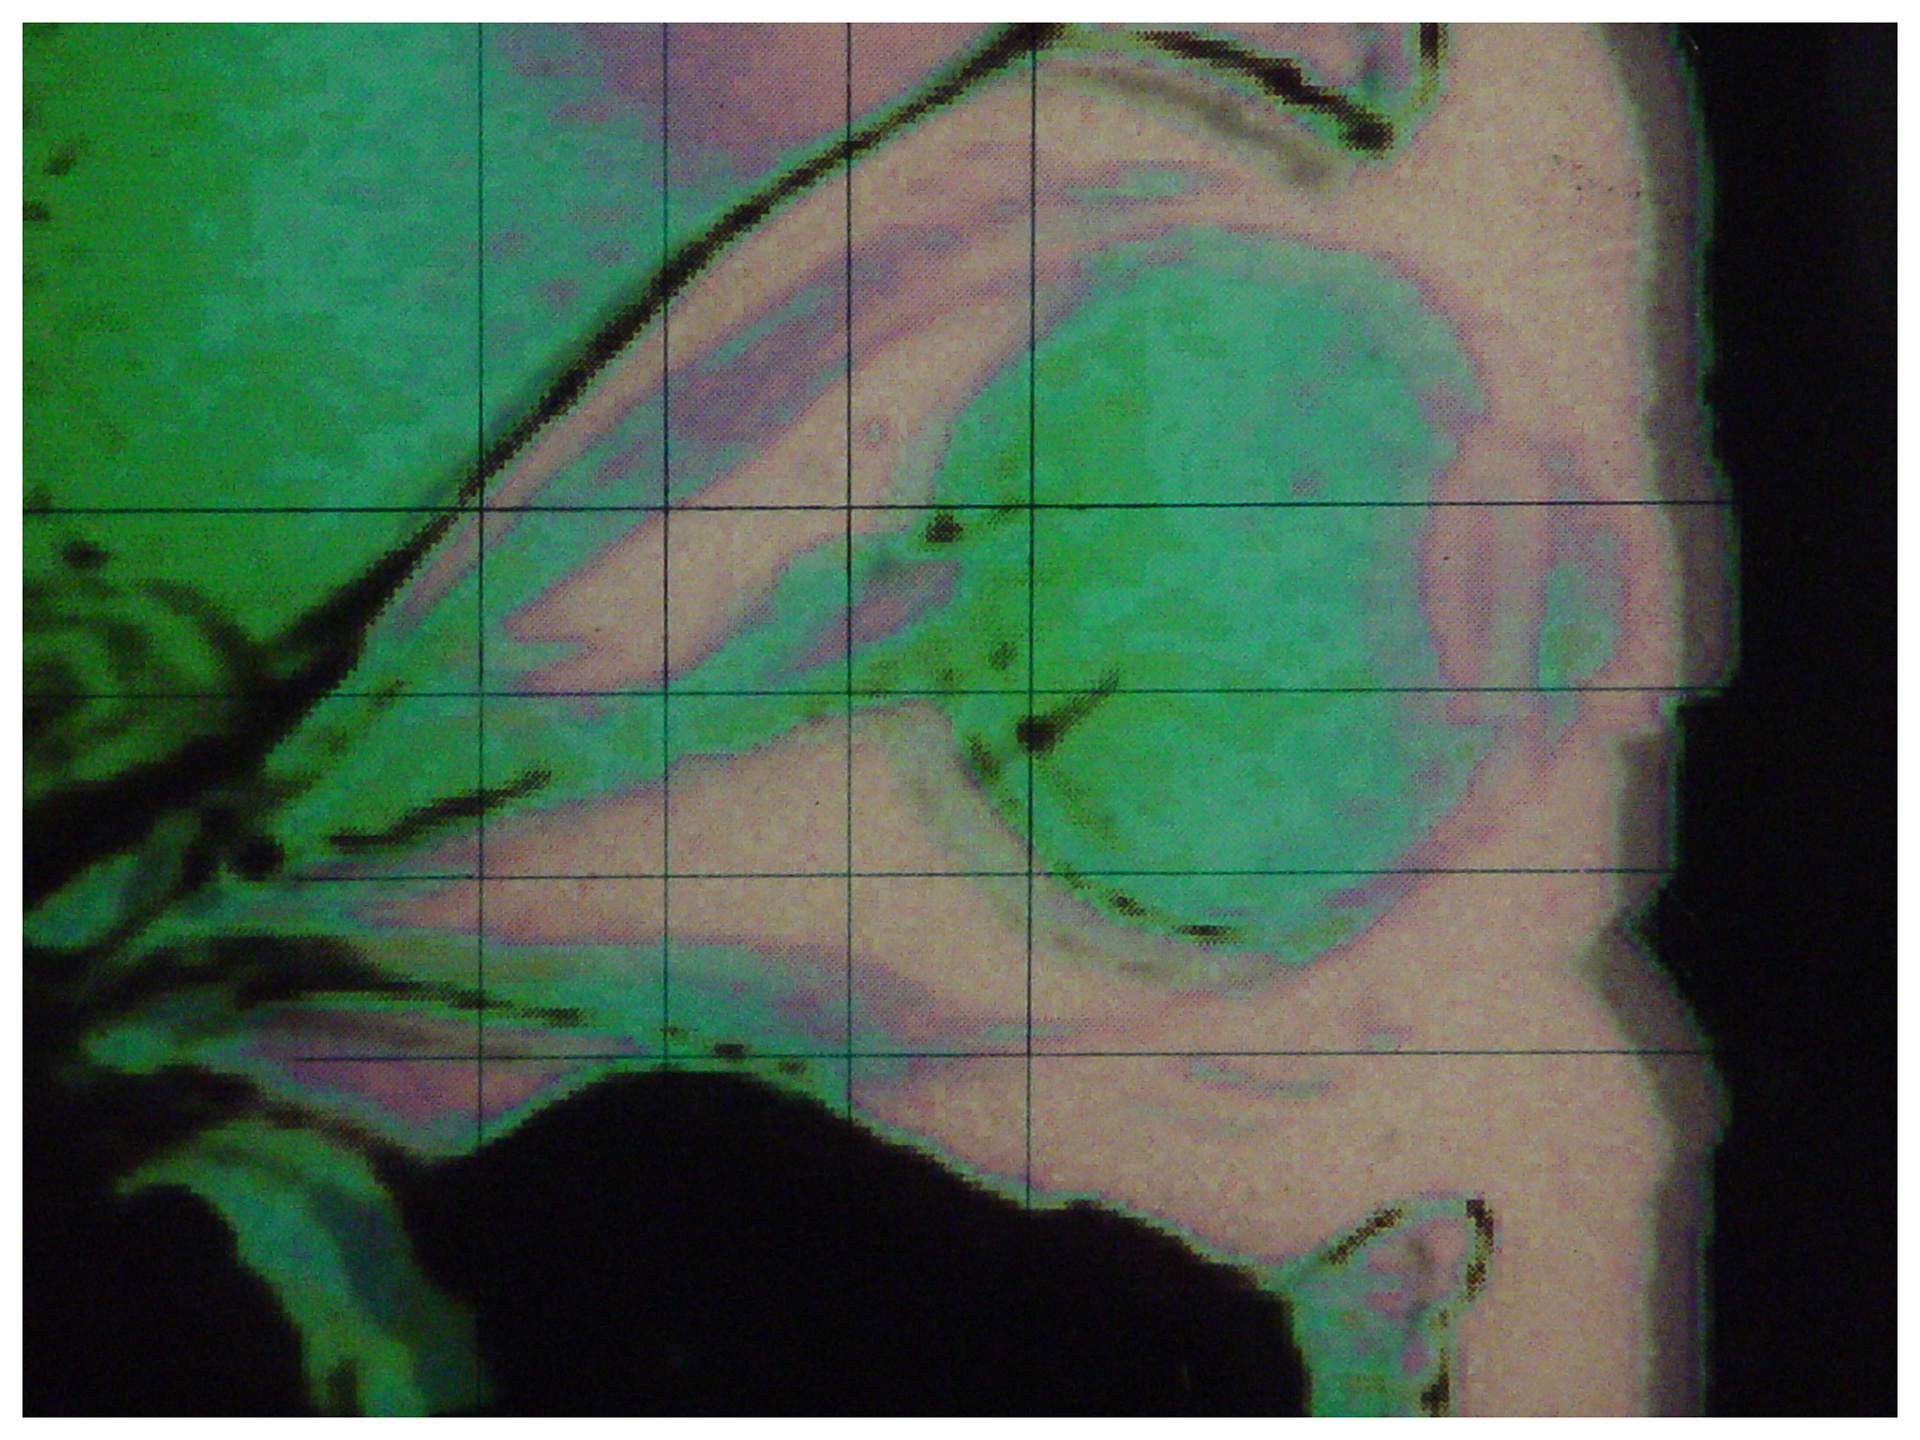

In Hebrew mythology the Yester - a form of creative imagination - is positioned at the junction of the valves of the heart.

The abstract pattern in the work is also from my body - from my imagination. A DNA sample is included behind the pattern, alluding to a connection between the concept of DNA as a human program and the computer program. The energy expressed by the pattern is suggestive of some inherent potential in both imagination and the DNA.